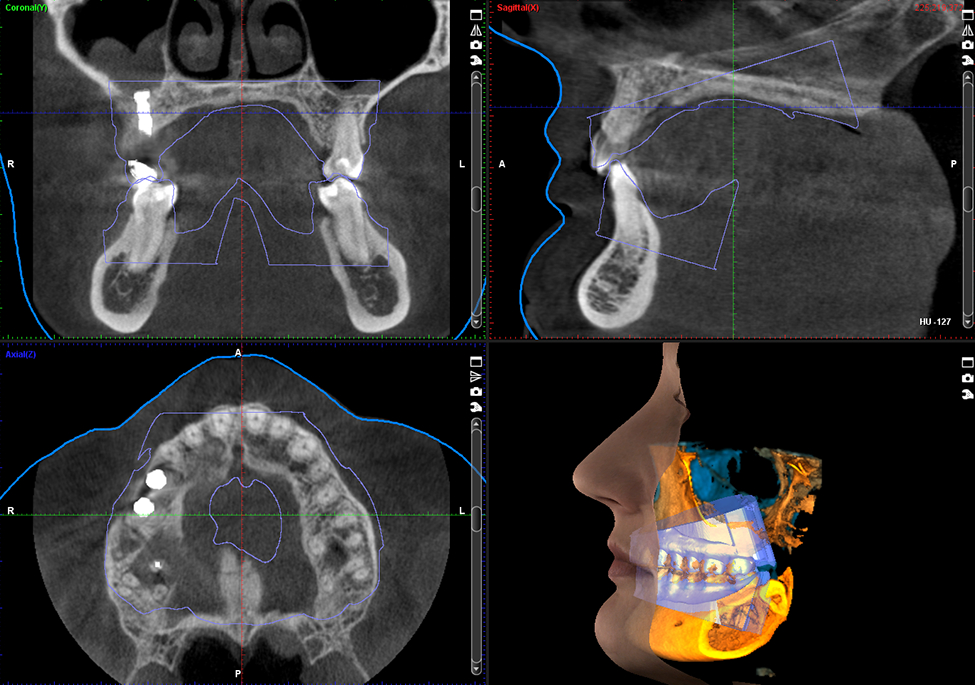

Chất lượng hình ảnh là một trong những yếu tố quan trọng nhất cần xem xét khi lựa chọn một thiết bị 3D. Tất cả các thiết bị của Planmeca đều cung cấp chất lượng hình ảnh tuyệt vời khi sử dụng giao thức hình ảnh Planmeca Ultra Low Dose ™. Nhưng đừng vội tin chúng tôi – bạn có thể tự mình kiểm định chất lượng từ những hình ảnh 3D bên dưới.

Tuy nhiên, cần phân biệt giữa một phim có giá trị chẩn đoán cao với một “phim đẹp”. Có giá trị chẩn đoán cao là phim cung cấp được cho bác sĩ lâm sàng nhiều thông tin từ một bức phim, có thể thấy được những chi tiết nhỏ nhất cho mục đích phát hiện các vấn đề ý nghĩa cho bệnh nhân. Sơ suất trong hiển thị phim có thể dẫn đến những chẩn đoán thiếu chính xác hoặc lập kế hoạch sai. Vì vậy cả việc chụp và hiển thị hình ảnh phim cũng